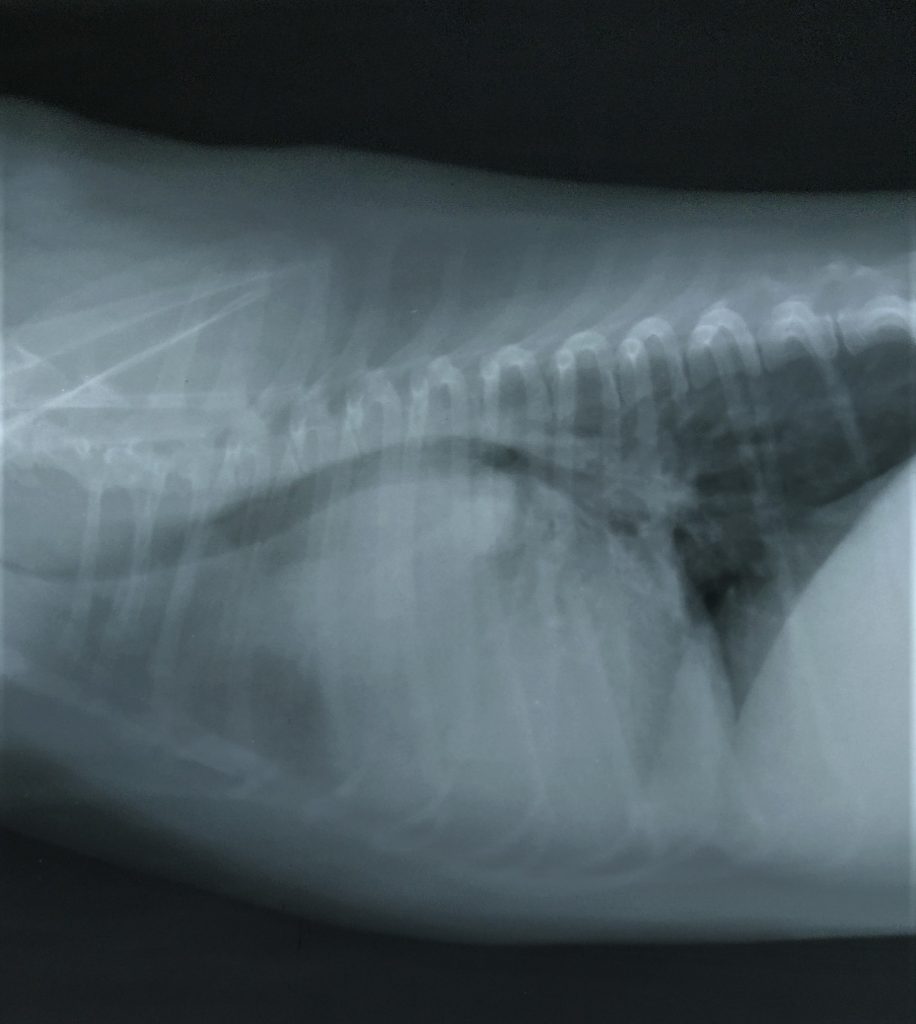

Estudio Radiográfico

Pruebas realizadas por su veterinario y aportadas a DXIA.

Desplazamiento traquea cranealmente, perdiéndose el ángulo normal que debe tener con la columna. Cardiomegalia derecha sobre todo zona aurícula derecha o base cardíaca. Edema perihiliar leve.

Se observa estructura de densidad tejido blando que se superpone en zona de la silueta cardíaca, correspondiente a la zona de la aurícula derecha produciendo efecto silueta. Cardiomegalia. Aerofagia. Pulmón sin patrón alterado.